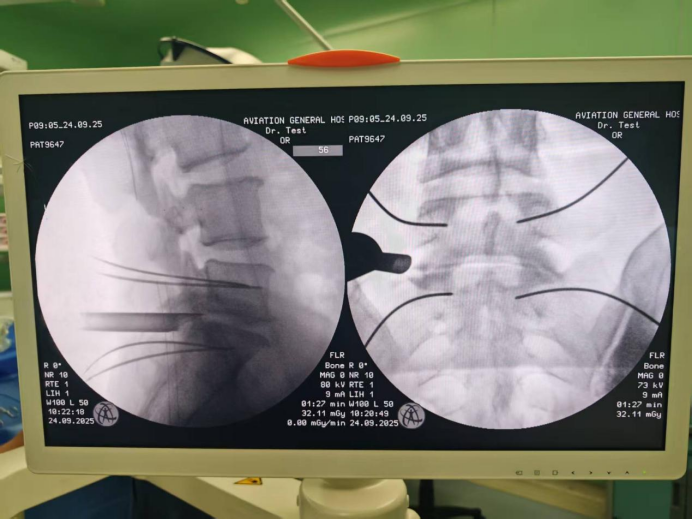

机器人辅助下椎弓根钉导丝和减压套管位置良好

术中,铸正机器人系统搭载的直观图像定位技术发挥了关键作用。该技术可结合术前CT与术中X光片,通过双圆环定位标尺,将术前生成的三维手术路径,映射到术中二维X光中,引导机械臂完成术中定位。全程定位精准且流程简易迅速,有效缩短了术中操作时间,极大减少了患者创伤。